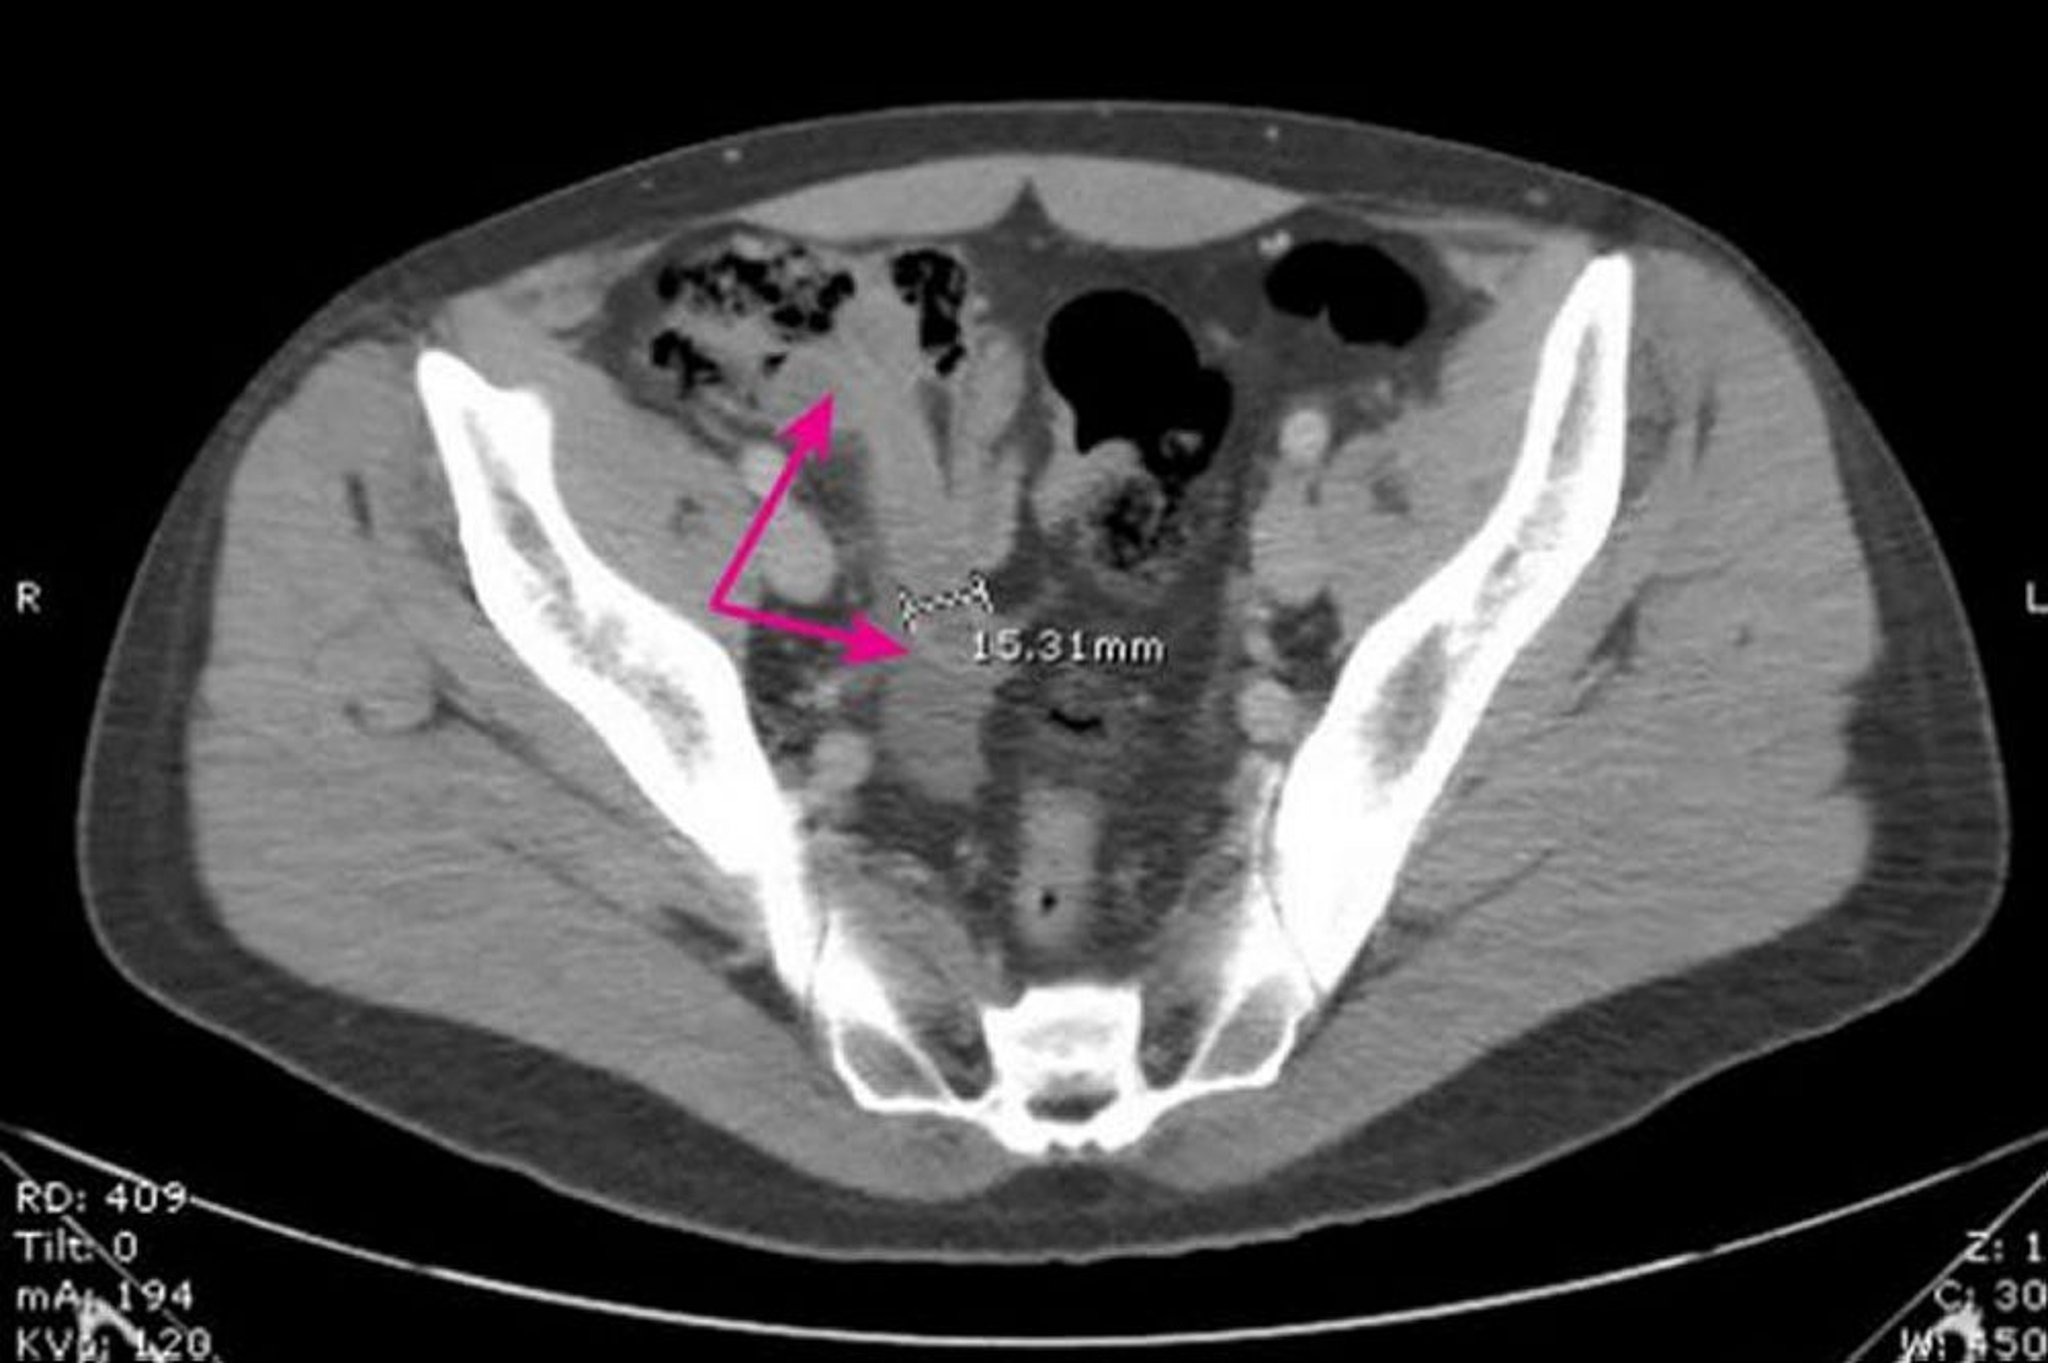

Hình ảnh này cho thấy ruột thừa giãn ra, có thành dày (mũi tên) có đường kính 15,31 mm với những thay đổi viêm xung quanh.

Hình ảnh do bác sĩ Parswa Ansari cung cấp